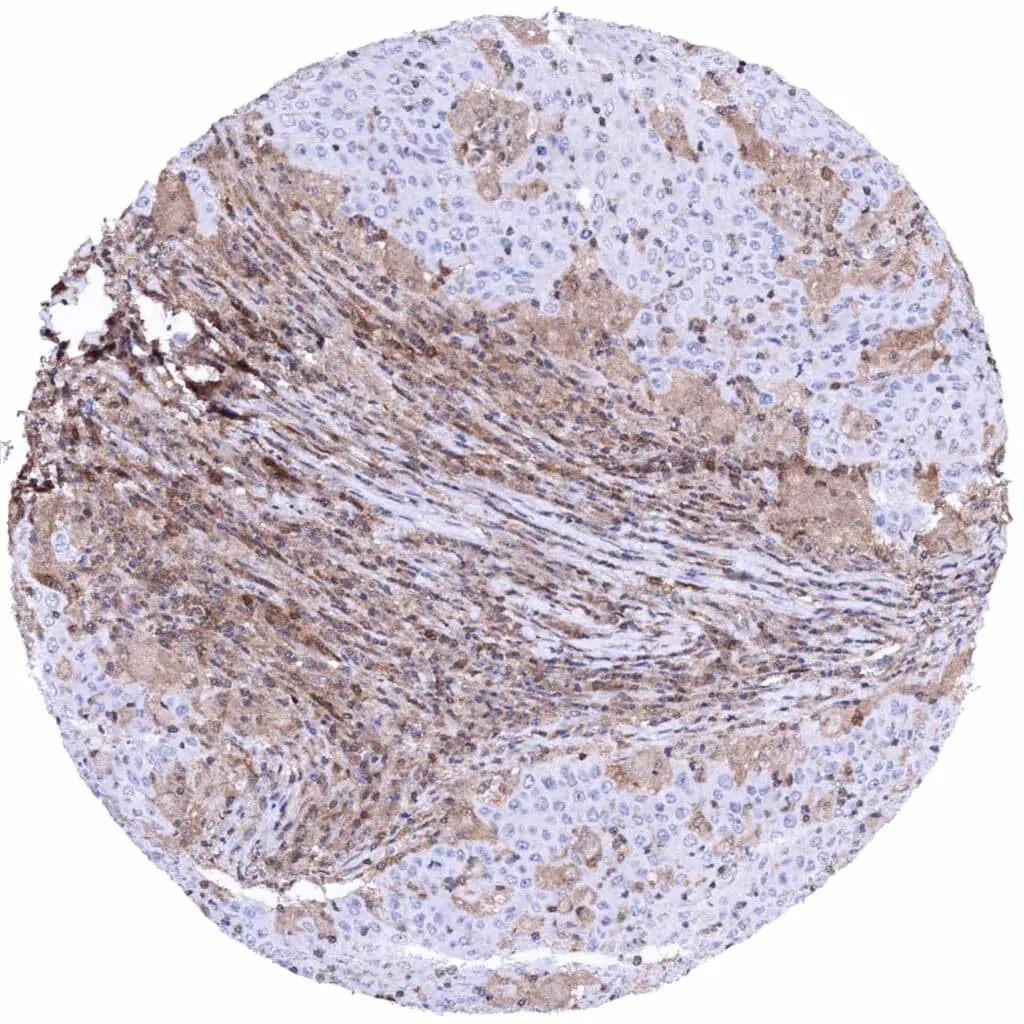

Soft tissue – Malignant peripheral nerve sheath tumor (MPNST) with complete absence of MTAP staining in tumor cells